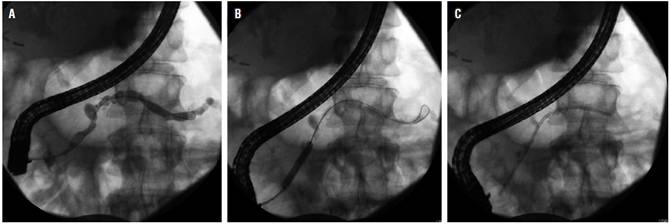

Terapia endoscópica para las estenosis del ducto principal

Se observan estenosis en el CPP principal hasta en el 18 % de los pacientes con PC y la prioridad es descartar malignidad. Similar al principio y a los problemas creados por cálculos obstructivos, se piensa que esta estenosis contribuye a los síntomas porque causa hipertensión ductal pancreática; entonces, la terapia es dirigida a mejorar estos segmentos estrechos para descomprimir al sistema ductal. El abordaje usualmente involucra la esfinterotomía pancreática, seguida por la dilatación de la estenosis y la colocación de un stent en el ducto pancreático (Figura 3). El alivio inmediato y sostenido del dolor con este tratamiento se ha reportado en 65 %-95 % y 32 %-68 % de los pacientes, respectivamente 20.

Actualmente, la colocación de un solo stent de polietileno de 10 Fr con cambios sucesivos por 1 año, incluso en ausencia de síntomas, es el tratamiento de primera línea de la estenosis dominante del CPP 6.

Una técnica en estudio para tratar las estenosis del ducto principal que persisten más allá de los 12 meses después del manejo con un único stent plástico es el despliegue de múltiples stents de plástico colocados lado a lado simultáneamente 22.

En un estudio colaborativo multicéntrico internacional se demostró que el drenaje del ducto pancreático por USE en las estenosis pancreáticas después de una CPRE fallida es un procedimiento seguro, mínimamente invasivo con respecto a la cirugía e incluso más efectivo 23.